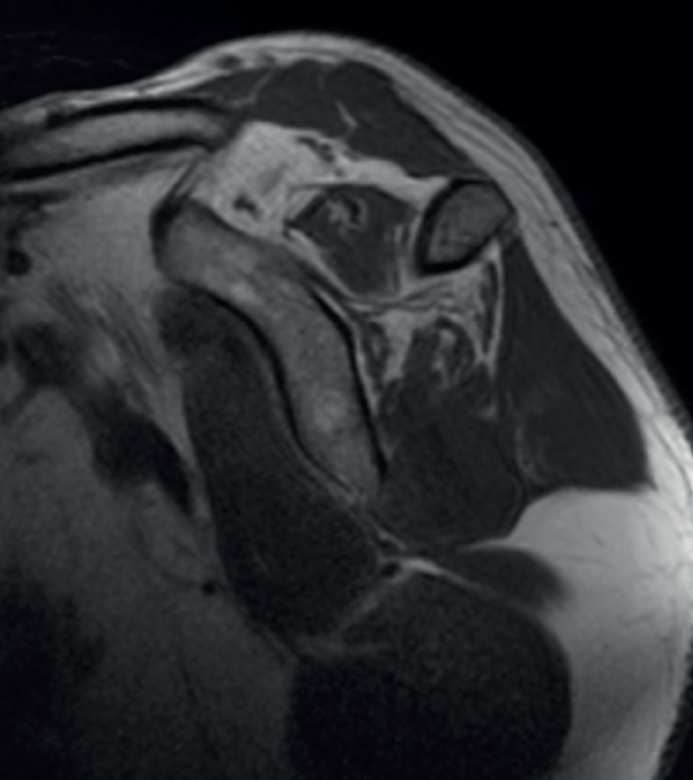

Figura 1. Corte coronal de resonancia magnética.

En la radiografía se descartó ascenso de la cabeza humeral, así como otros signos de artropatía. En la resonancia magnética se apreció una rotura posterosuperior (Collin de tipo D)(20) de manguito retraída a la glena (Patte 3)(21) con atrofia grasa (Goutallier 2-3)(4) de los tendones supra- e infraespinoso (Figuras 1 y 2). Ante estos hallazgos clínico-radiológicos se estableció el diagnóstico de rotura masiva de características no reparables, por lo que se propone realizar una transferencia tendinosa con trapecio inferior.